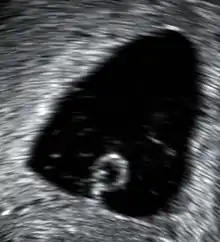

A 13-week fetus without cardiac activity located in the uterus (delayed or missed miscarriage)

A missed miscarriage is when the embryo or fetus has died, but a miscarriage has not yet occurred. It is also referred to as delayed miscarriage, silent miscarriage, or missed abortion.[102][103]